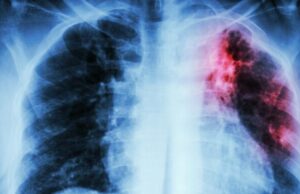

Туберкулозата е најзаразна болест на светот

Туберкулозата сега е најзаразната болест на планетата, надминувајќи ги Ковид-19 и СИДА-та, бидејќи секој ден одзема 4.000 животи, од кои 700 се детски...